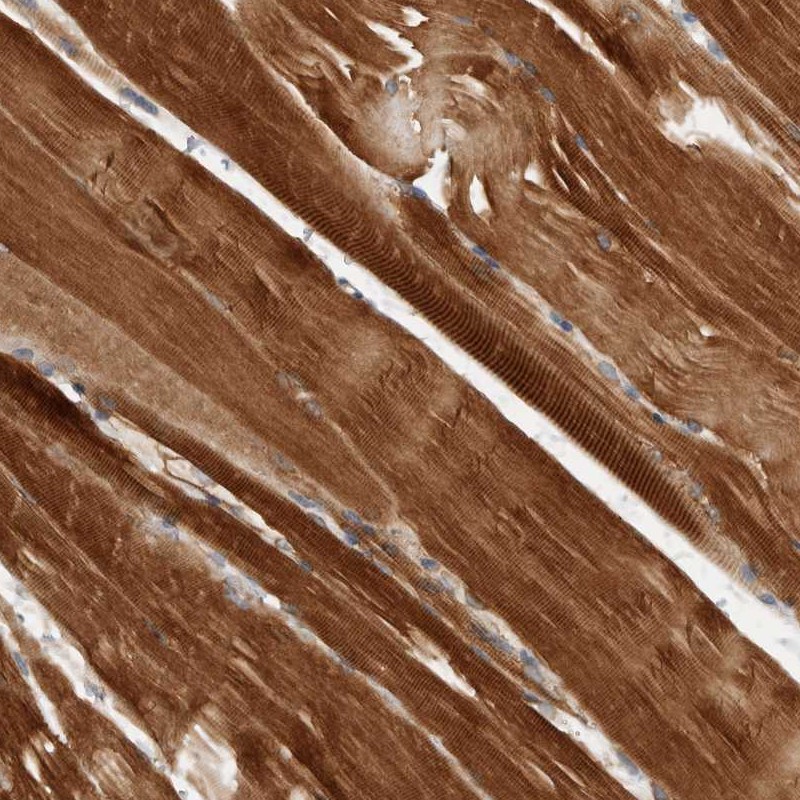

Immunohistochemical staining of human skeletal muscle shows strong cytoplasmic positivity.